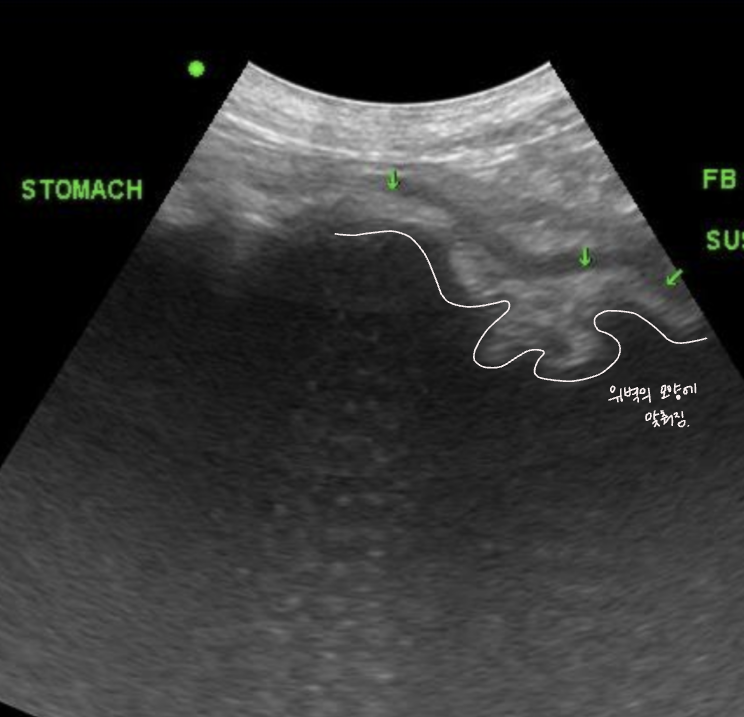

- ์๋ด ์กฐ์์ ๊ฐ ์ถ์ ๋จ. (gastric emptying ์ง์ฐ)

- ์์์ด duodenum์ผ๋ก ๋์ด๊ฐ์ง ๋ชปํด ๊ตฌํ ์ฆ์.